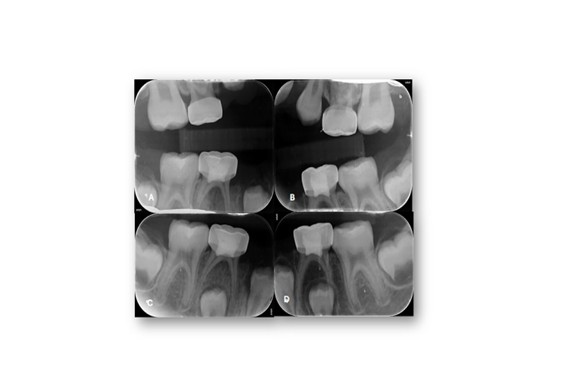

Figure 3: Selected periapical radiographs. A-D) According to the AAPD Guidelines for Prescribing Dental Radiographs, when evaluating a new patient in the mixed-dentition stage for dental disease and developmental assessment, an individualized radiographic examination should include a panoramic radiograph supplemented by posterior bitewings and selected periapical images as indicated.

Figure 7: Post-Operative Selected periapical and bitewings radiographs. A-D) Post-operative views showing restored teeth, resolution of carious lesions, and improved periapical status following treatment.